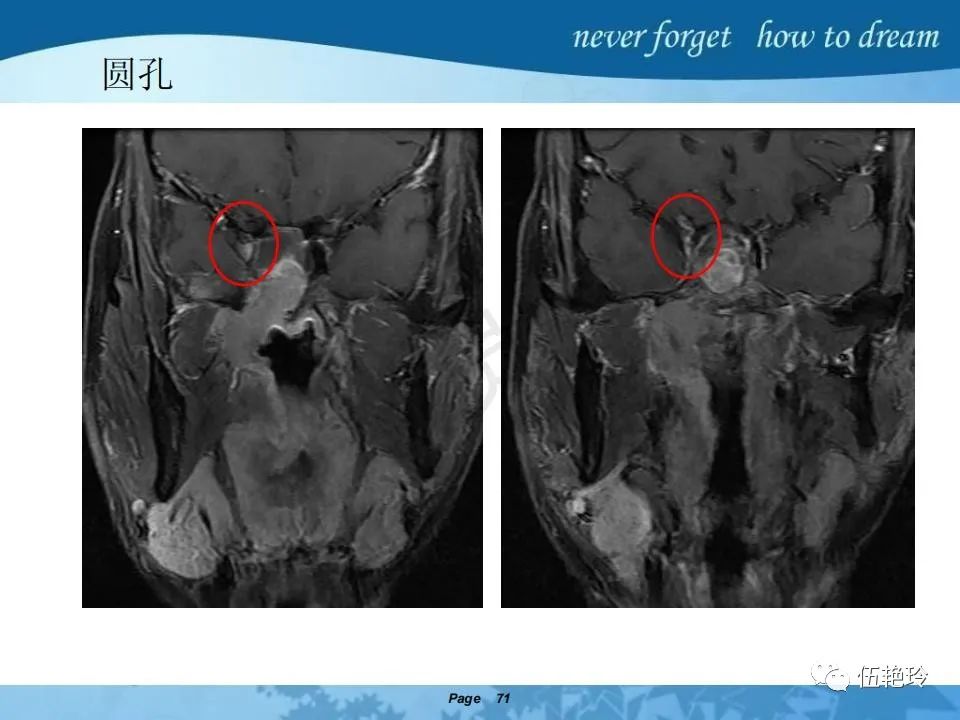

2.2 鼻咽特有的解剖途径:鼻咽癌原发灶循序进展的总途径:鼻腔(47.8%)→翼腭窝(15.2%)→ 眶下裂(3.2%)→眶尖(1.2%)→海绵窦(0.6%)。

2.31 向上颅内:①鼻咽顶壁→破裂孔(岩尖、斜坡)→蝶窦、海绵窦;②鼻咽顶壁→蝶骨基底部→蝶窦、海绵窦;③鼻咽侧壁→茎突前间隙→蝶骨大翼(卵圆孔)→海绵窦;④鼻咽侧壁→茎突前间隙→翼腭窝→ 颞下窝;⑤鼻咽前壁→鼻腔→翼突、翼腭窝→眶下裂→眶尖→海绵窦;⑥鼻咽前壁→鼻腔→上颌窦、筛窦;